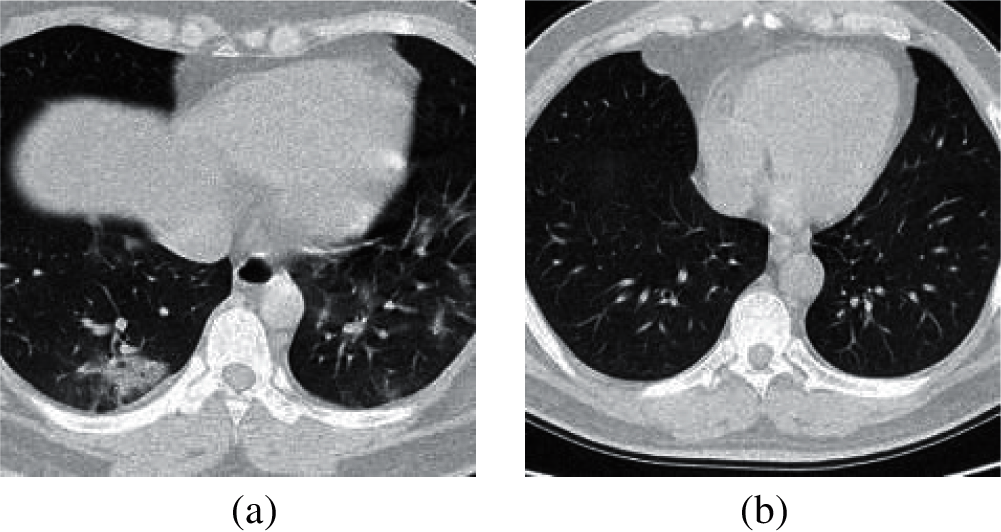

The image slices we collected came from 142 COVID-19 patients and 142 healthy people. From the CT images of each subject, 1–4 slices were selected as experimental data, and the resolution rate of all images was 1,024 × 1,024. Table 1 shows the characteristic data of the collected objects. In Fig. 1, we can find that the lung biopsy samples of COVID-19 patients have obvious white lesions.

Figure 1: The sample of lung slices from patient with COVID-19 and healthy person. (a) COVID-19 (b) Normal